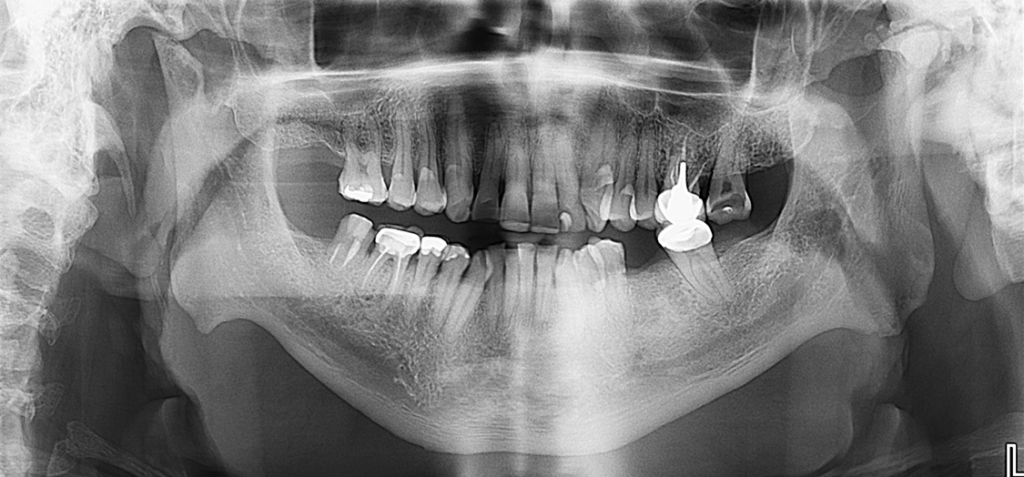

Radiografia Panorámica

En la radiografía panorámica se evidencia aplanamiento de ambos cóndilos mandibulares con acentuación bilateral de las escotaduras antegoniales. En el cóndilo mandibular izquierdo se observa esclerosis acompañada de imágenes radiopacas circundantes, compatibles con cuerpos óseos libres.